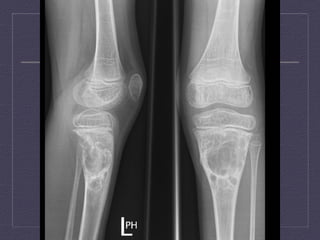

Giant  Cell  Tumor     Benign,  metaepiphysis  of  long  bones       Early  adulthood  (  20-­‐  50  y.o)     Single  lesions  (knee,  distal  radius,  sacrum)     X-­‐Ray  and  CT  :  occurs  only  with  a    closed  epiphyseal   plate,  ar:cular  surface,  well  defined  with  non-­‐ sclero:c  margin,  periosteal  reac:on  (10-­‐30%  cases),   no  calcifica:on     MRI:  low  signal  in  T1WI  and  T2WI     Angiography:  hypervascular  tumor  with  the  rest   being  hipo/avascular